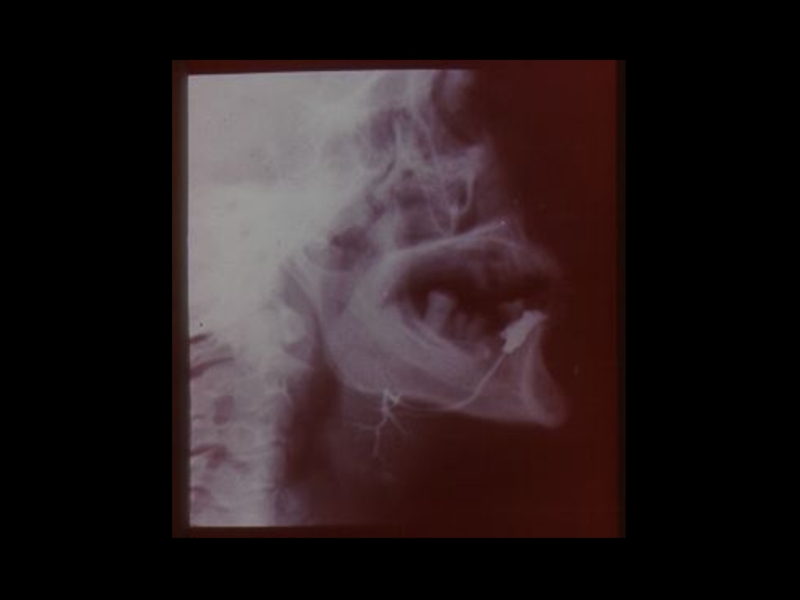

Слайд 18Методы традиционной рентгенодиагностики:

1. Общие методы

(рентгеноскопия, рентгенография)

2. Частные

методы

(флюорография, томография,

электрорентгенография, маммография и

другие)

3. Специальные методы

(урография, бронхография, ангиография,

лимфография, пневмоартрография и другие)

Методы традиционной рентгенодиагностики:1. Общие методы   (рентгеноскопия, рентгенография)2. Частные методы   (флюорография, томография,